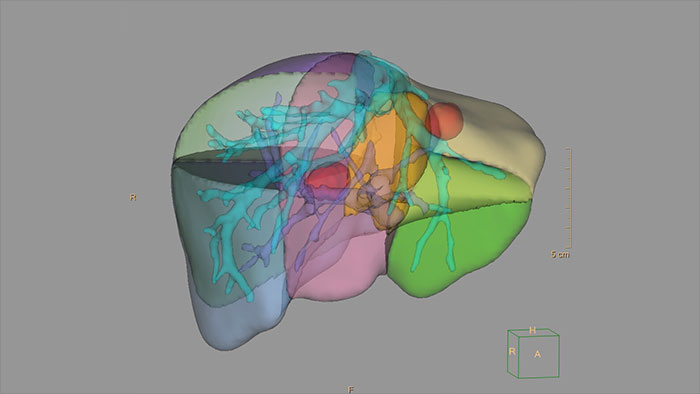

Streamlined modeling workflow

Allows to view volumetric images of anatomical structures, perform segmentation, edit and combine segmented elements (tissues) into a 3D model.